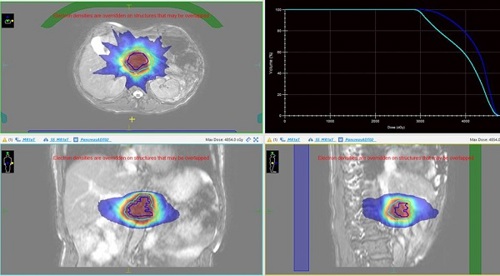

Moving onto the technical news, we have expanded the patient cohorts we treat on the MR-Linac. In May 2022, we treated our first patient with pancreatic cancer. These tumours can be difficult to see with the conebeam CT (CBCT). Using MR imaging we can better visualise target improve treatment accuracy. Using our Adapt to Shape (ATS) online re-planning, the interdisciplinary team can re-contour the position of organs close to the tumour daily and then plan the treatment according to that position.

Below is a picture of a treatment plan for a patient with a pancreas tumour. Note the high dose region in the red colourwash, covering the target (plus a margin for breathing motion) in the blue and cyan lines.